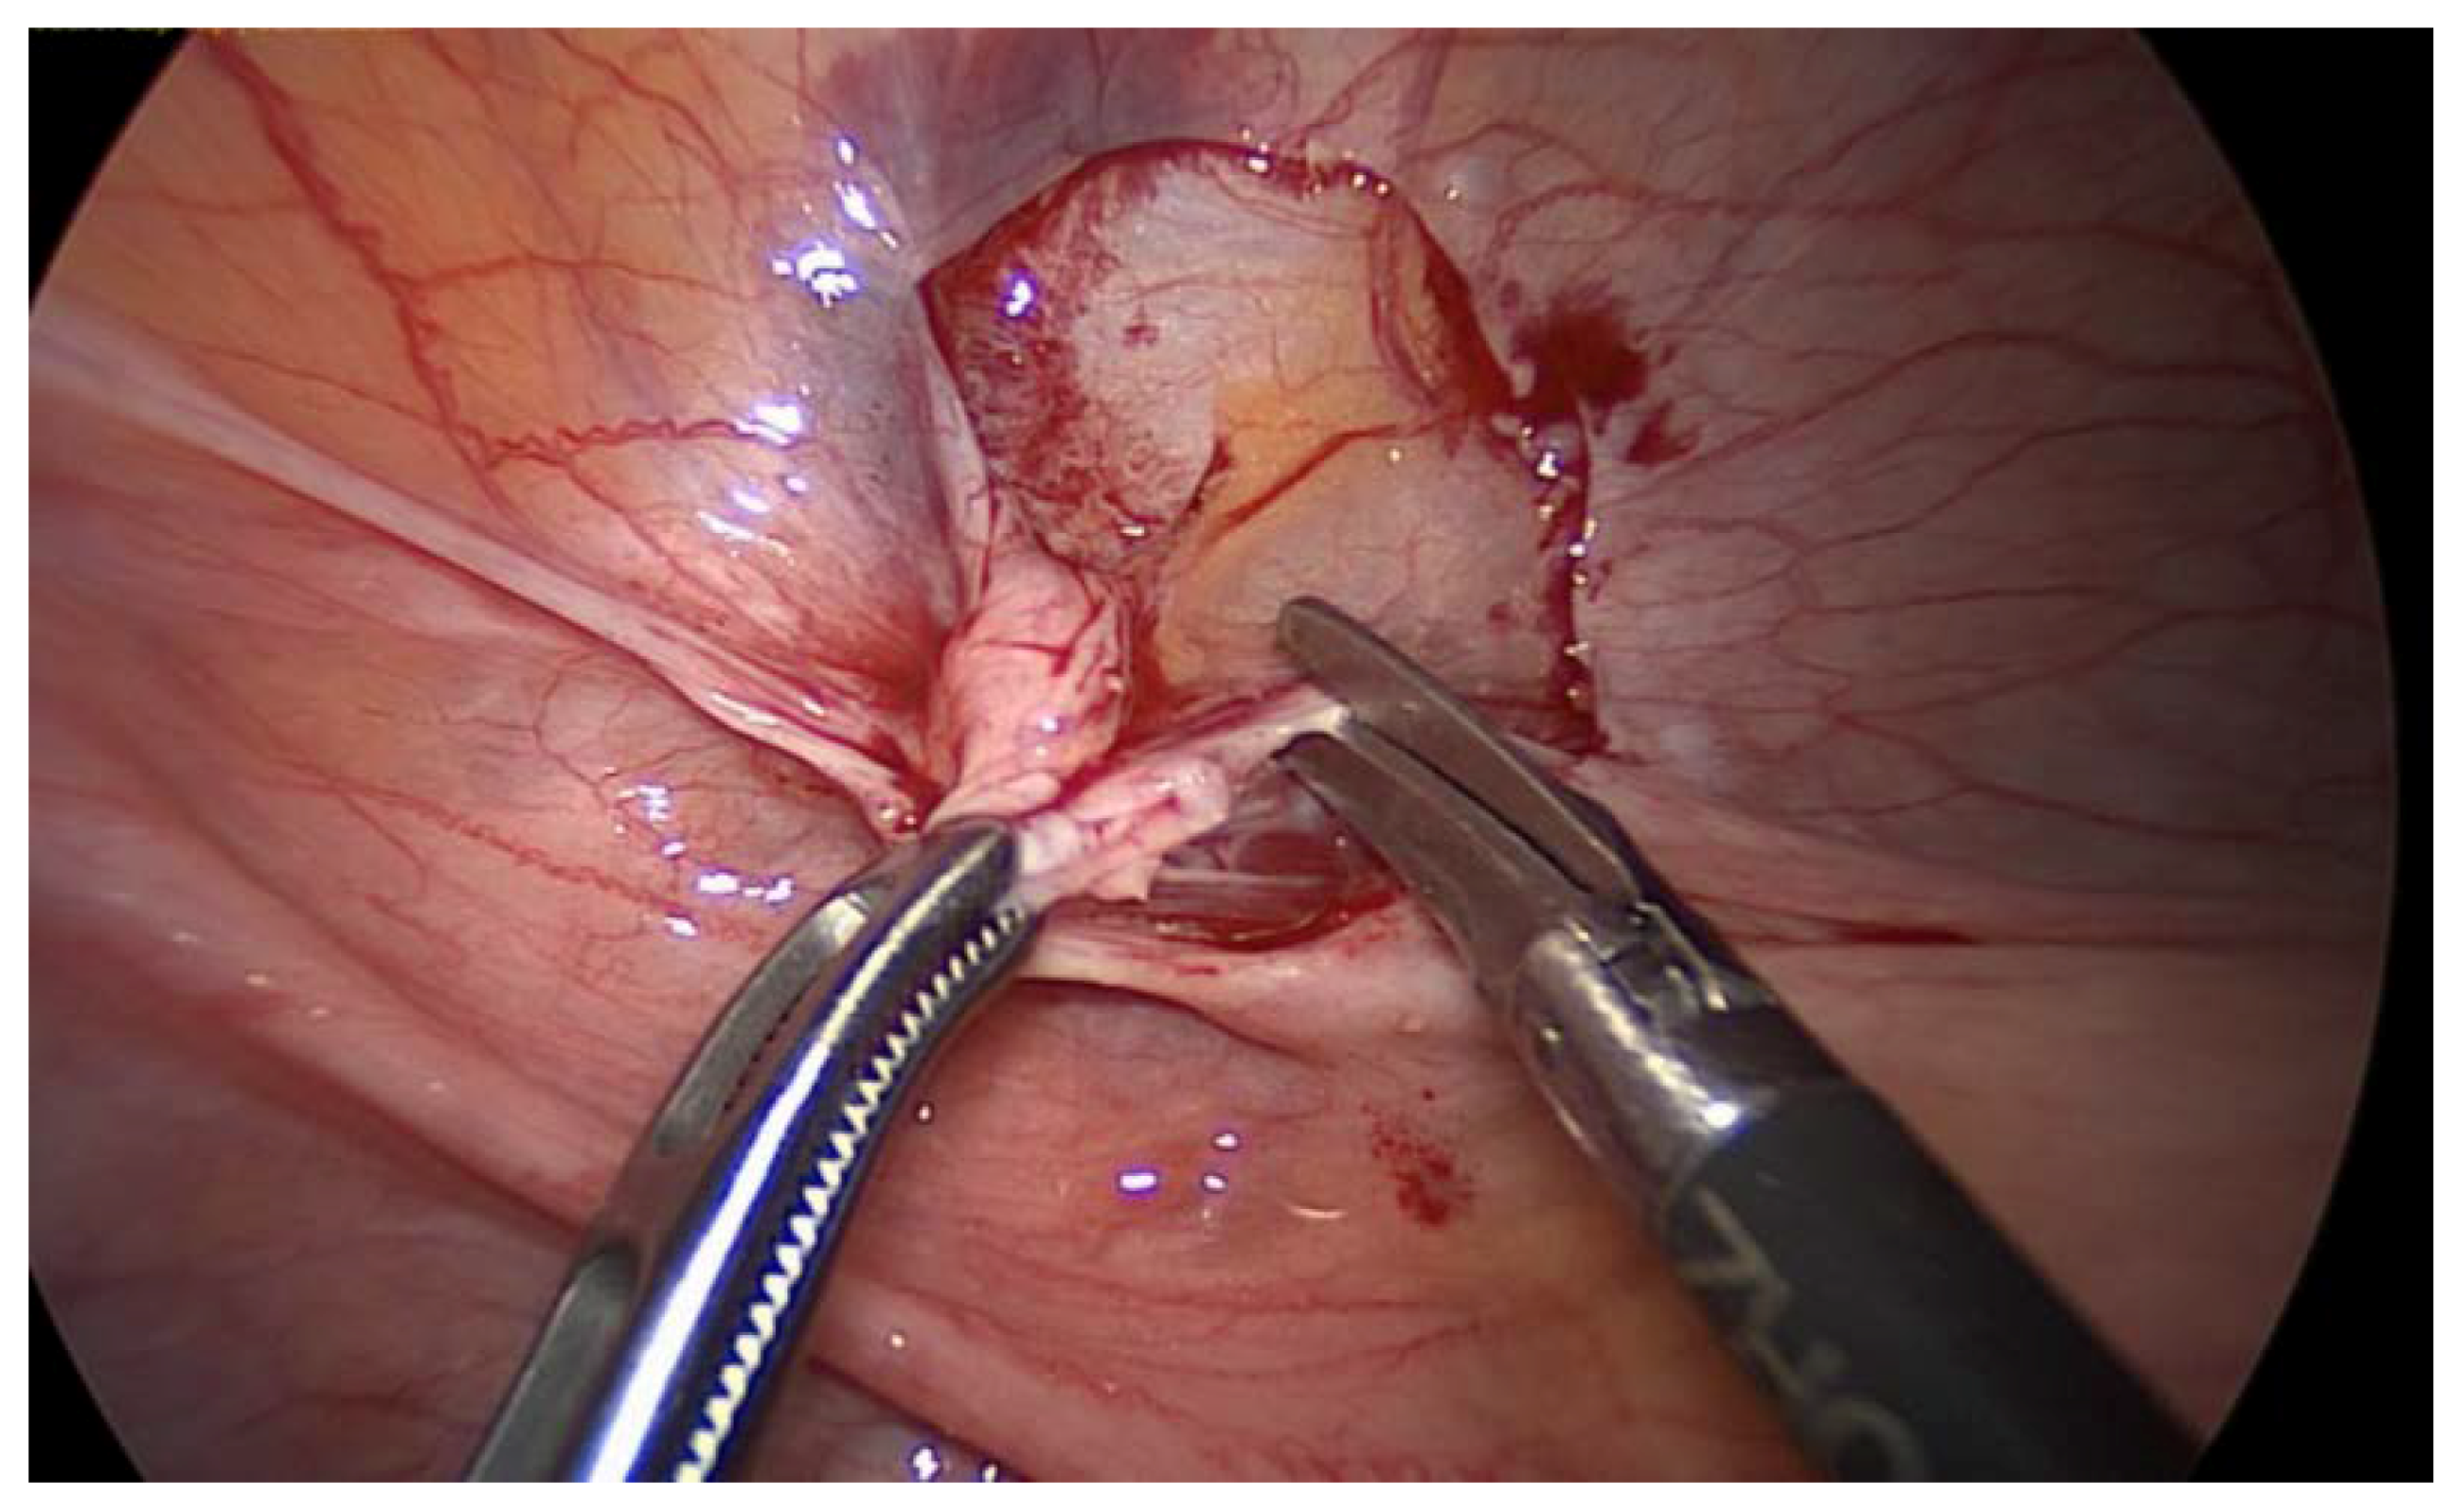

2. Case Report